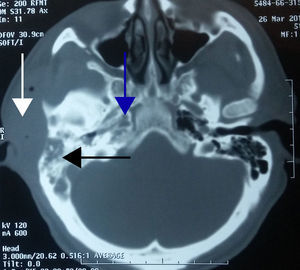

Caso 4Paciente masculino de 52 años con antecedente de enfermedad renal crónica manejado con diálisis peritoneal, referido al servicio con otorrea derecha de un mes de evolución y aumento de volumen en región retroauricular ipsilateral, secundario a traumatismo 7 días previos. En la TC se encontró edema en tejidos blandos en región temporal, una otomastoiditis y un absceso cerebral en lóbulo temporal (fig. 4). El paciente fue tratado mediante craniectomía descompresiva, capsulectomía, drenaje del absceso parenquimatoso, mastoidectomía con muro bajo y drenaje del absceso retroauricular (fig. 5).

En el caso 4, en el paciente con una enfermedad renal crónica llama la atención el absceso cerebral, por ser un hallazgo incidental. Clínicamente el paciente no tenía síntomas de afectación neurológica; la TC contrastada se realizó para descartar absceso de tejidos blandos, porque 7 días previos a su valoración había presentado traumatismo craneoencefálico en dicha zona al caerle una escalera. Se confirmó el diagnóstico de absceso cerebral por hallazgos imagenológicos. Dentro de la fisiopatología del absceso cerebral, el oído medio tiene una importancia capital en el inicio de la infección intraparenquimatosa debido a la frecuencia de las otitis medias y la posibilidad de difícil control al pasar a la cronicidad en fase de actividad. Es difícil de tratar en ocasiones por lo cerrada que está la cavidad del oído medio ya que sus paredes están en contacto con hueso neumatizado que favorece el avance y la diseminación de los gérmenes a los compartimientos intracraneales. Cuando la otitis es el factor predisponente afecta más frecuentemente el lóbulo temporal o el cerebelo. Una vez hecho el diagnóstico se debe realizar la cirugía de urgencia dirigida a evacuar la colección de pus y para el lavado constante con antibiótico. Es importante recordar el estrecho espacio de la fosa posterior en la que masas de crecimiento rápido causan la súbita degradación del estado de conciencia y la apertura del absceso dentro del cuarto ventrículo3.